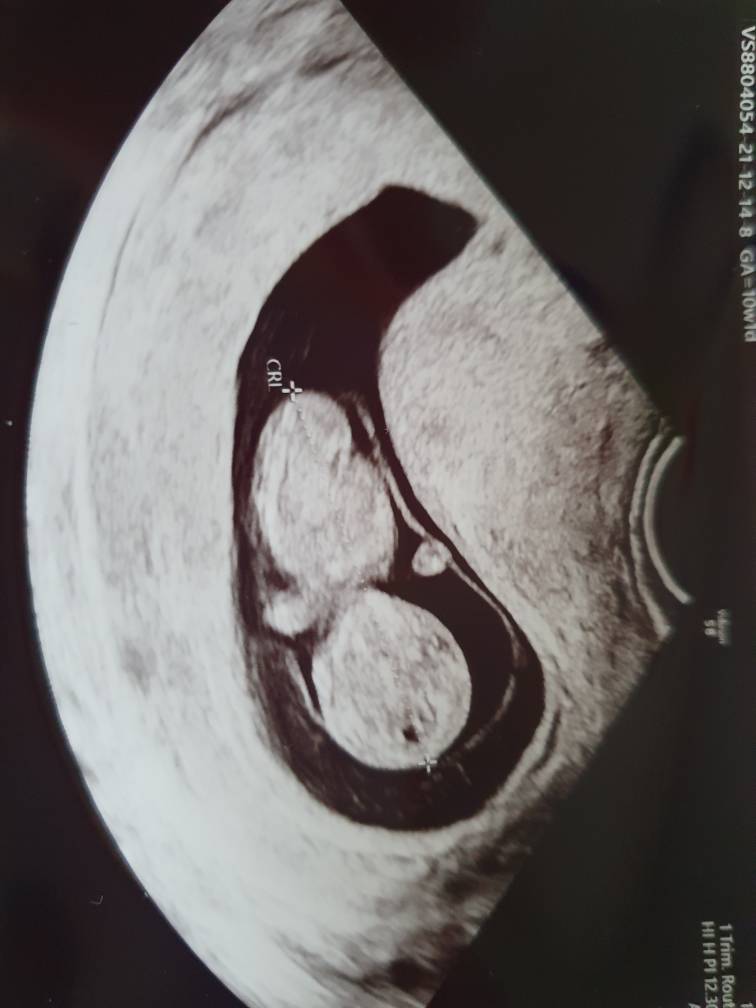

Oooo to i kluseczka, z usg termin porodu wychodzi na 6.07.

20211214_101103.jpeg

A ja się zastanawiam nad prenatalnym bo wyczytałam że jedna kobitka miała większego dzidziusia niż wg OM i 13tc to może być za późno na prenatalne. A ja właśnie w tym tyg sobie ustawiłam. Moje dzieciątko jest na razie większe o 3-4dni i sama nie wiem co myśleć. Następna wizyta u lekarza to 28.12 to będzie wg OM 10+2 a wg USG 10+6. Mam nadzieję że w tym dniu dowiem się czegoś wiecej.

Dzidziuś musi mieścić się w przedziale 4,5 cm do 8,5 cm. Jeśli będzie większy to może być problem ze sprawdzeniem przezierności karkowej.

Tak więc wszystko zależy od tego jak duży jest Twój maluch, dowiesz się na kolejnej wizycie.